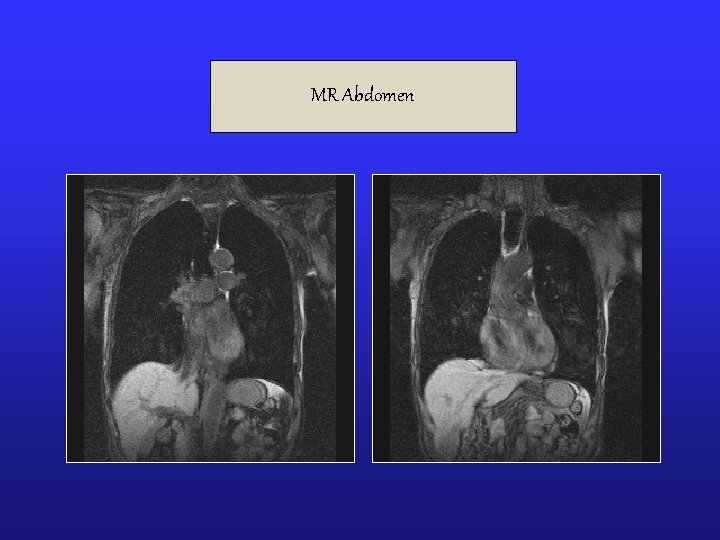

Radiological Investigations § X-Ray Chest PA (12/11/03): No significant abnormality detected. § USG Abdomen (12/11/03): No significant abnormality detected. § Doppler examination of carotid, vertebral, abdominal aorta and peripheral arterial system of lower limbs were quite normal. § MRI of Brain, Neck & abdomen was unremarkable. § MR Angio of Brain. § MR Oesophagus: Normal study § MR cholanigopancreatography: Normal study § MRI Abdomen – pelvis : Presence of bowel gas, etc were seen. Gall bladder collapsed. Urinary bladder partially filled with urine around 70 ml.

MR Abdomen